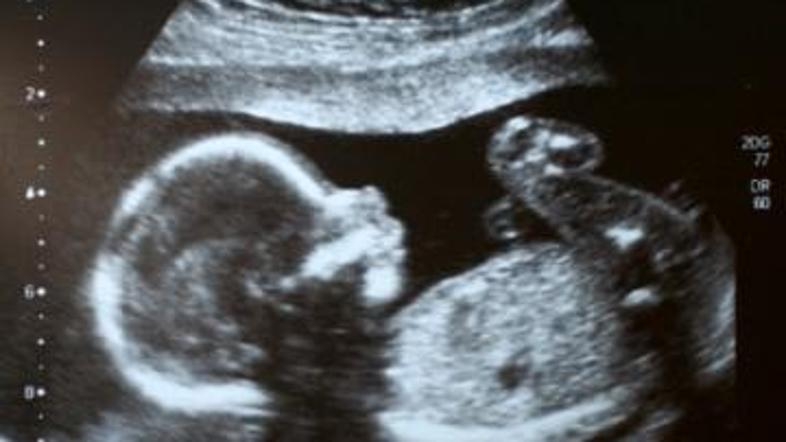

ultrazvok Žurnal24 main